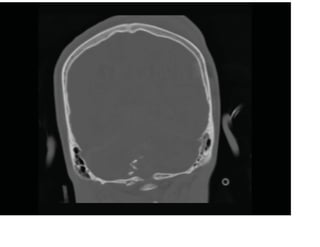

Fenêtres osseuses avec balle logée

Les données du scanner peuvent

être reformatées dans le plan

coronal pour évaluer les fractures

du calvaire.